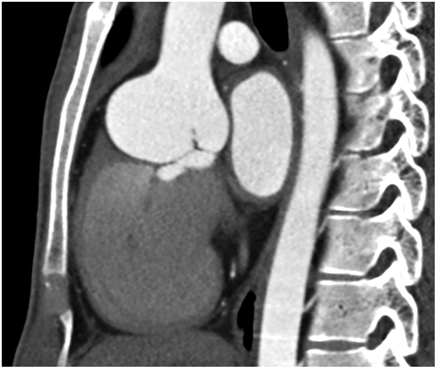

右バルサルバ洞瘤に対する手術例Surgical Repair of the Right Sinus of Valsalva Aneurysm Using an Artificial Vascular Graft Patch